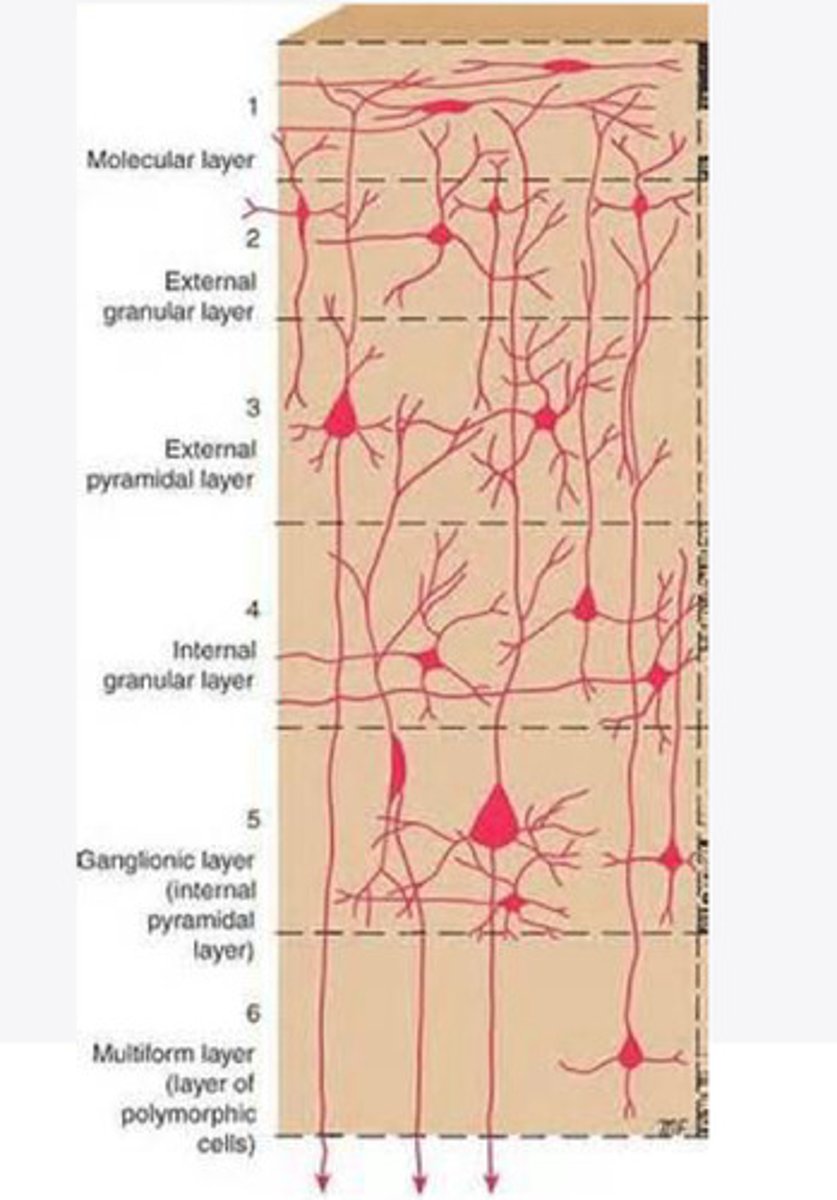

divided into 6 distinct layers, due to varying densities of cell body types within each layer

The cortex of the brain is divided into how many layers? Why is it divided into layers?

Layers of the cortex of the brain pic

2 and 4

What are the layers of the cortex that are associated with input?

3 and 5

What are the layers of the cortex that are associated with output?

molecular layer

What is the name of Layer 1 of the cortex of the brain?

very few cells

Does Layer 1 of the cortex have a lot or few cells?

receives dendrites from internal layers so it may actually function as a coordinating center where layers can communicate action

What does Layer 1 of the cortex do?

1

Every layer sends densities to Layer ____?

1

What layer serves as the "water cooler" of the brain?

external granular layer

What is the name for layer 2 of the cortex of the brain?

receives input from other cortical regions

What is the function of Layer 2 of the Cortex of the brain?

Stellate

What type of cells (stellate/pyramidal) would be most concentrated in Layer 2?

external pyramidal layer

What is the name for layer 3 of the cortex of the brain?

sends output to the other cortical layers

What is the function of Layer 3 of the cortex of the brain?

pyramidal

What type of cells (stellate/pyramidal) would be most concentrated in Layer 3 of the brain?

Layers 2 and 3

What layers are associated with association and commissural fibers?

Layer 3 - axons of cell bodies

Layer 2 - synapse into target areas in Layer 2

What part of the axons is in Layer 2/ in layer 3?

Layer 3 - external pyramidal layer

All axonal cel bodies for association and commissural fibers lie within what layer of the Cortex of the brain?

internal granular

** or called the striate cortex because it is so thick that you can see a line through this layer even in unstrained brain slides

What is the name for the 4th layer of the cortex of the brain?

receives input from the thalamus, geniculocortical layer, and other brainstem areas

What is the function for the 4th layer of the Cortex of the brain?

very thick within the vision, auditory, and somatosensory areas

Is Layer 4 thick or thin within SENSORY areas of the cortex?

Internal pyramidal

What is the name for Layer 5 of the cortex of the brain?

sends axons to the brainstem (corticobulbar) and spinal cord (corticospinal)

What is the function of Layer 5 of the cortex of the brain?

in motor areas of the cortex?

Where is layer 5 very thick in the brain?

the frontal lobe -- very motor heavy

What lobe of the brain will have a thick layer 5 of the cortex of the brain?

the multiform layer

What is the name of layer 6 of the cortex of the brain?

-sends axons back to the thalamus through corticogeniculate fibers

-modulates what information the thalamus sends to the cortex to control the strength of the signal received and modulate what you pay attention to

What is the function of layer 6 of the cortex of the brain?

no

Is layer 6 a motor layer?